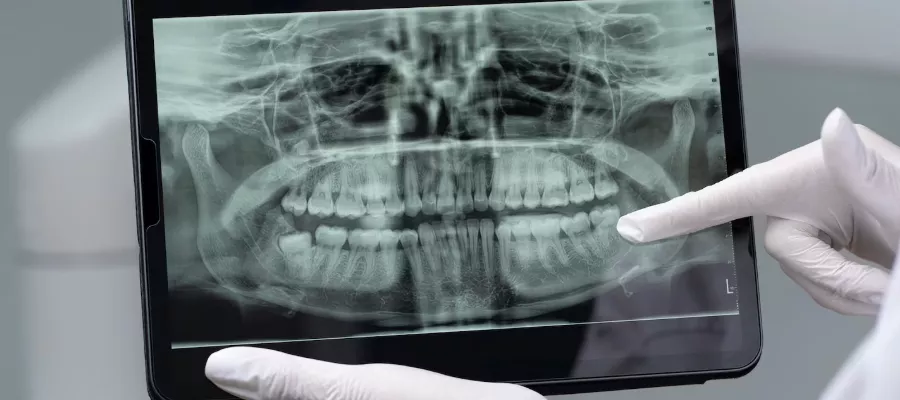

Dental Panoromik X-Ray, ağız ve dişlerin genel görünümünü gösteren radyografik iki boyutlu görüntüleme tekniğidir. Dişlerin, çene kemiklerinin ve diş etlerinin tek bir filmde izlenmesine olanak tanıyan film, tüm diş hekimliği olarak kullanılır.

Dental panoramik X-ray; ağız içindeki birçok önemli yapının görülmesini sağlayan bir tür radyoloji tekniğidir. Dişler, çene kemikleri, diş eti kanalları ve sinüs boşlukları bu görüntüleme yöntemiyle birleşik olarak çekilir. Çürükler, enfeksiyonlar ve periodontal hastalıklar dahil olmak üzere birçok oral patoloji tipini bu görüntüleme yardımıyla doktorlar tespit edebilir .

Ayrıca, dişlerin kök uzunlukları, eklem pozisyonları ve yönleri gibi önemli özelliklere göre tedavi planlanabilir İmplant tanılama ve tedavileri; protez tanılama ve tedavileri gibi uygulamalar yararlanacağı radyolojik bir incelemedir . İmplant tedavisi ameliyatlarında yeterli alana veya yüksekliğe stres vermeme en önemli kısıtlayıcı faktördür.